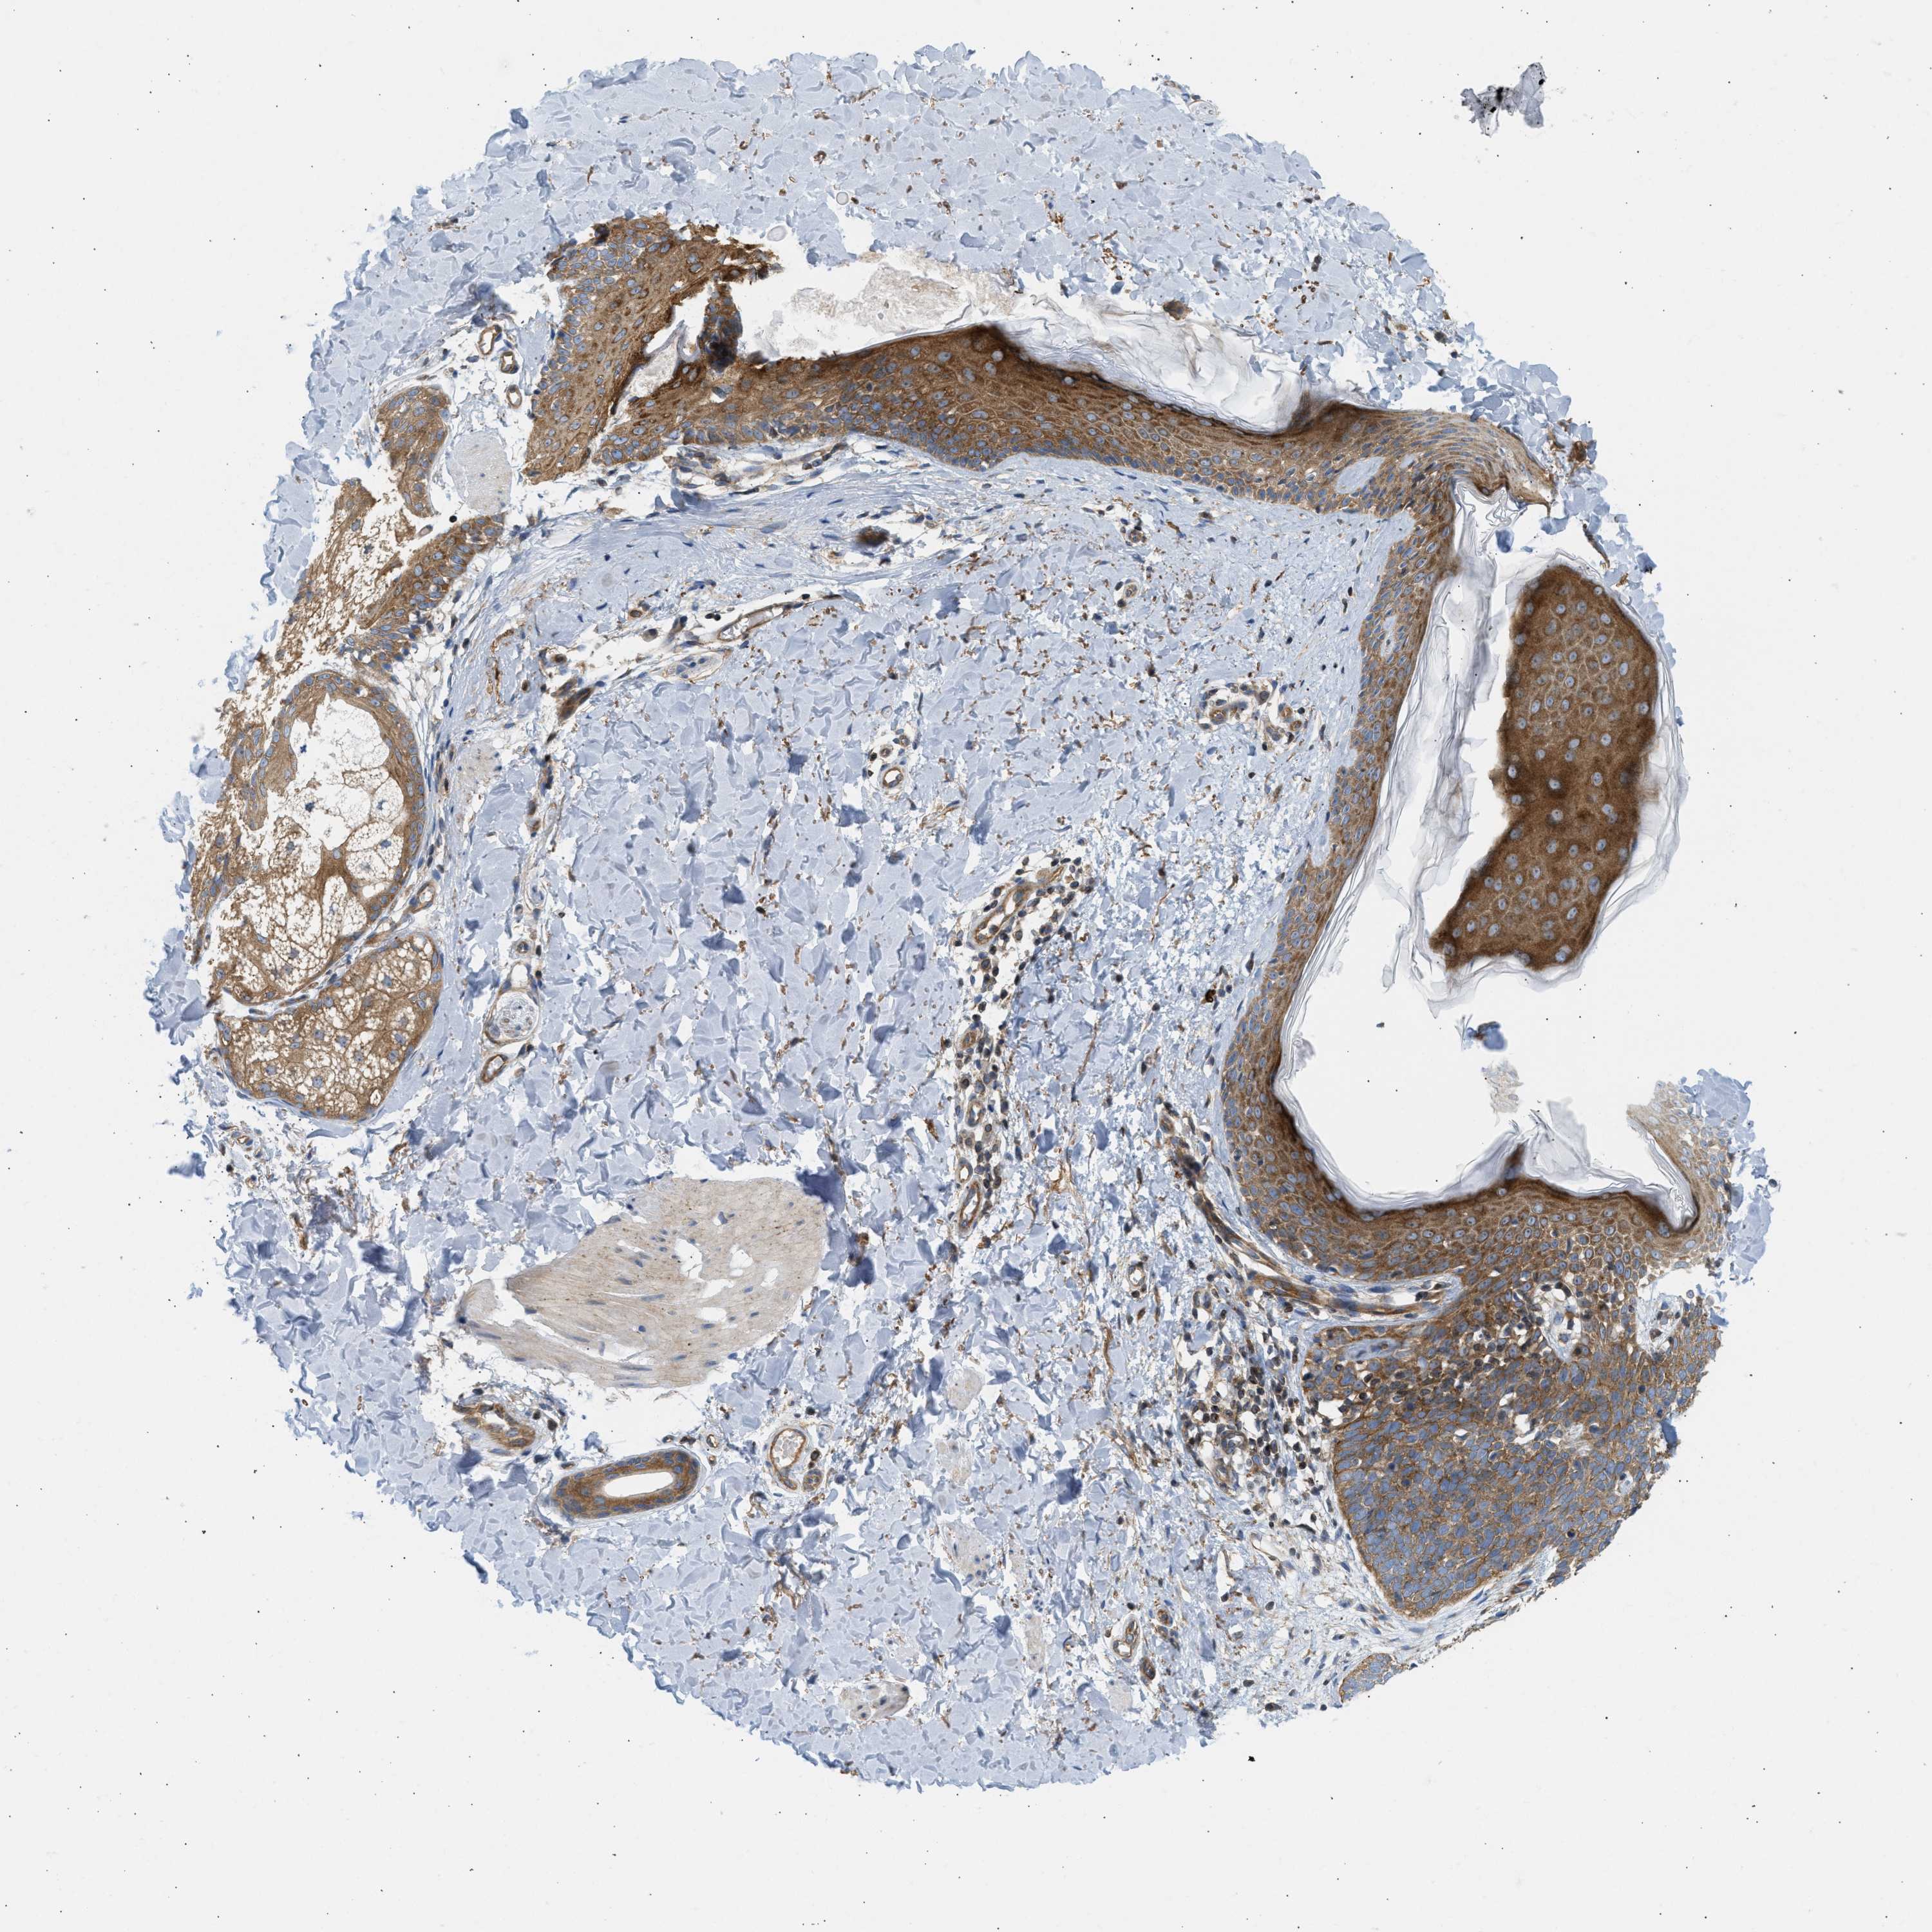

SKIN CANCER - Protein expressioni

A mouse-over function shows sample information and annotation data. Click on an image to view it in a full screen mode. Samples can be filtered based on level of antibody staining by selecting one or several of the following categories: high, medium, low and not detected. The assay and annotation is described here.

Antibody stainingi

Antibody staining in the annotated cell types in the current human tissue is reported as not detected, low, medium, or high, based on conventional immunohistochemistry profiling in selected tissues. This score is based on the combination of the staining intensity and fraction of stained cells.

Each image is clickable and will lead to virtual microscopy that enables deeper exploration of all samples and also displays staining intensity scores, fraction scores and subcellular localization as well as patient and tissue information for each sample.

Antibody HPA017286

Staining

High

Medium

Low

Not detected

Intensity

Strong

Moderate

Weak

Negative

Quantity

>75%

75%-25%

<25%

None

Location

Nuclear

Cytoplasmic/membranous

Cytoplasmic/membranous,nuclear

Squamous cell carcinoma in situ, NOS

Squamous cell carcinoma, NOS

Squamous cell carcinoma, metastatic, NOS

Basal cell carcinoma

Adnexal tumor, benign